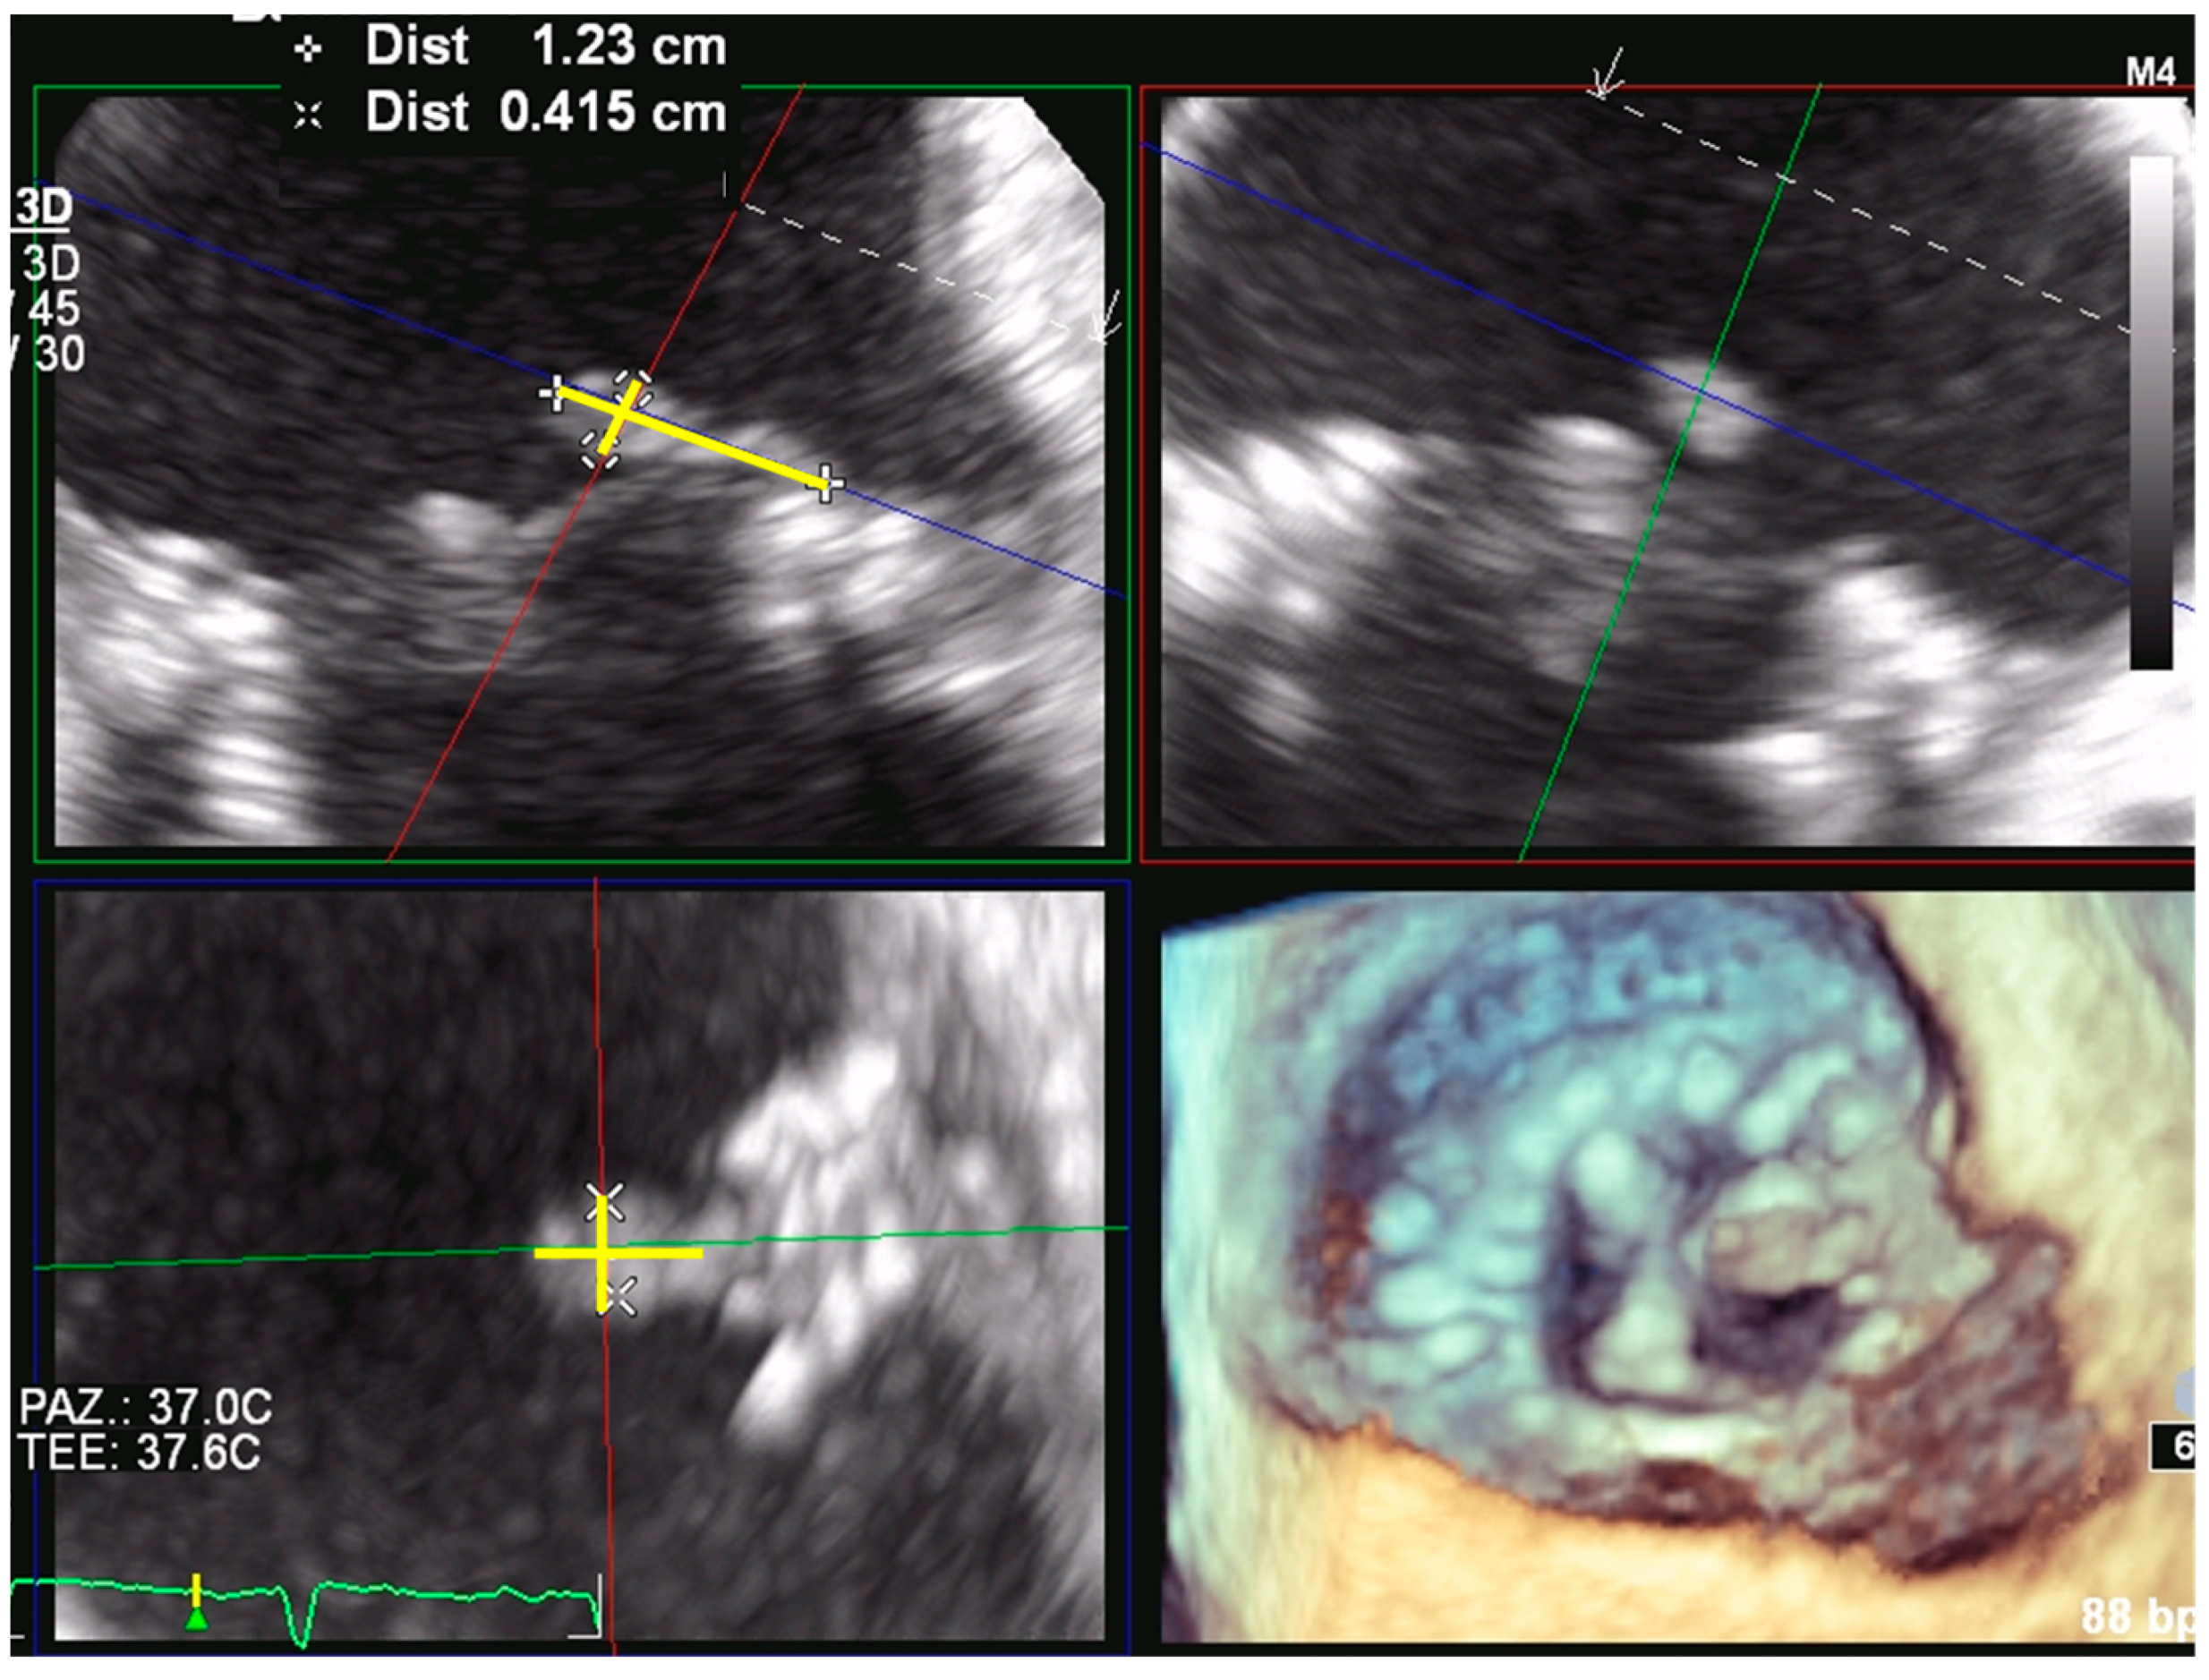

2. Prosthetic Valve Obstruction

2.1. Prosthetic Mitral Valve Obstruction